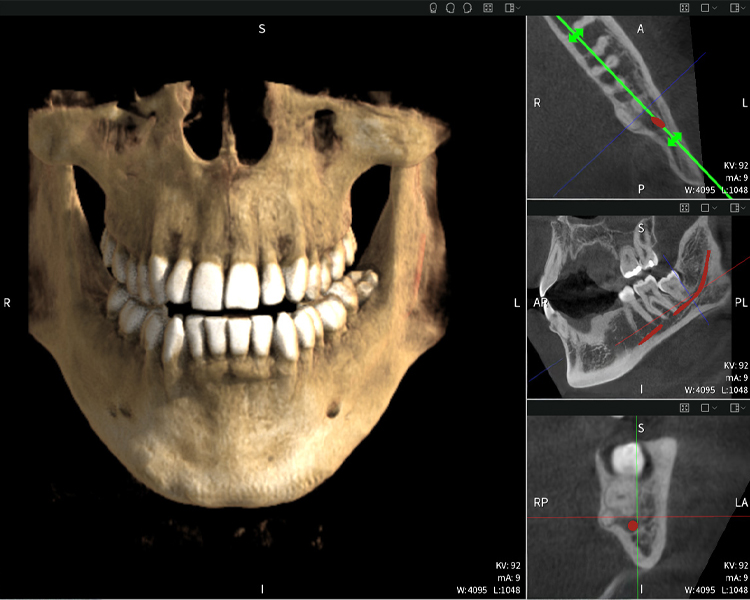

Nachstehend finden Sie einen Fall von Dr. med. dent. Oliver A. Centrella, in dem die CBCT-Aufnahmen mit Seethrough Max entscheidende Informationen zur komplexen Anatomie sowie zur kritischen Beziehung zwischen den Weisheitszähnen und dem Nervus alveolaris inferior lieferten. Bei diesem Fall besteht eine Indikation zur chirurgischen Entfernung der Weisheitszähne.

Abbildung a: Bildgebungsergebnisse von Seethrough Max vor einem schwarzen Hintergrund.

Abbildung a

• Oben links: Axiale Schnittansicht des linken Unterkiefers (Region 38) mit Darstellung des Nervus alveolaris inferior (rot) in unmittelbarer Nähe zu den Wurzeln des Zahns 38.

• Oben rechts: 3D-Rekonstruktion des gesamten Unterkiefers zur Orientierung. Der rot markierte Nervus alveolaris inferior verdeutlicht seine Lage im Kieferknochen.

• Unten links: Sagittale Ansicht des Unterkiefers (Region 38), die die enge räumliche Beziehung zwischen den Wurzeln und dem Nervenkanal verdeutlicht.

• Unten rechts: Koronale Ansicht des Unterkiefers (Region 38) entscheidend für die Beurteilung der räumlichen Lage der Wurzeln zum Nerven.